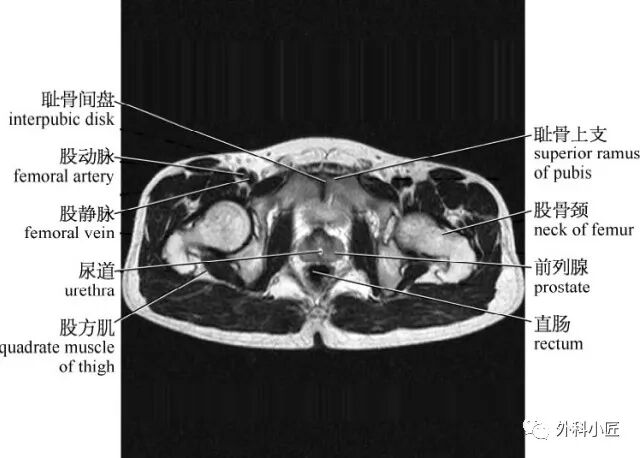

影像必备高清颅脑mr断层解剖图谱

图片尺寸728x634